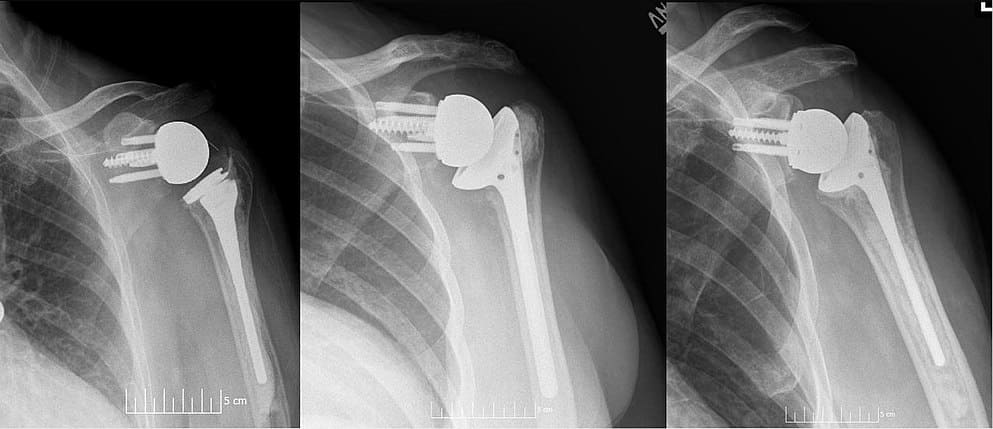

Bilateral Reverse Shoulder Replacement in an elderly lady, Who is now 85 years old. Right Reverse Shoulder done 8 years ago and left 4 years ago.

8 Years follow up Right RTSR, 4 Years follow up LEFT